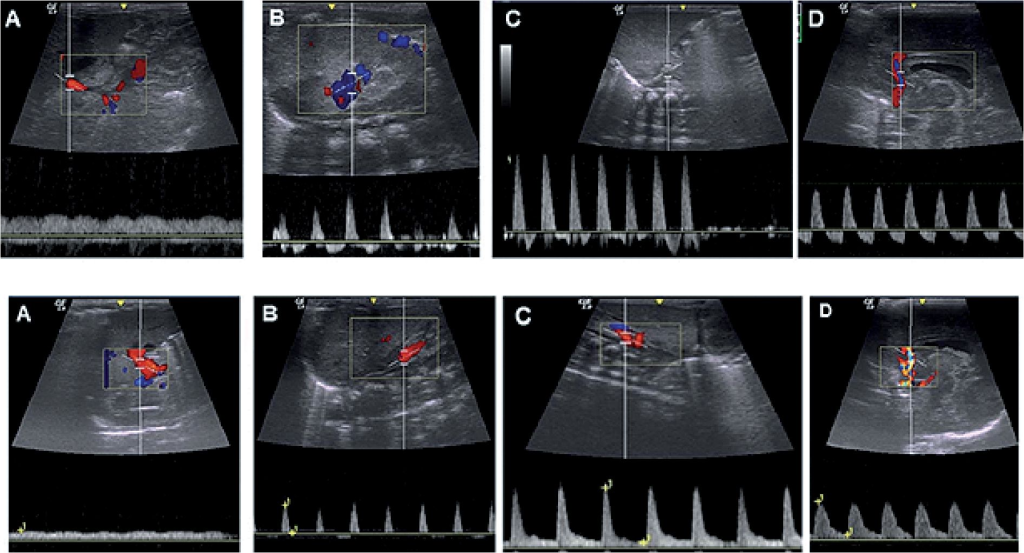

A) Las ondas Doppler espectrales de la arteria mesentérica superior (AMS ) en ayunas muestran un patrón de flujo de alta resistencia

(B) La imagen Doppler espectral de la AMS en estado posprandial de este paciente muestra un aumento en el intervalo de la velocidad sistólica máxima (VSM ) y la VTD. Obsérvese el aumento de la VTD a 55 cm/s.

La velocidad sistólica máxima y el índice de resistencia son particularmente importantes en la evaluación del riesgo de NEC, donde se visualiza IR>0.9.

Se ha observado que los neonatos que desarrollan NEC tienden a tener una velocidad sistólica máxima y un índice de resistencia más altos en la SMA durante el primer día postnatal.[1] Además, el flujo diastólico en la SMA y el tronco celíaco normalmente debe ser anterógrado, y cualquier alteración en este flujo puede indicar problemas hemodinámicos significativos.[3-4]